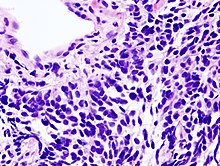

Small-cell lung carcinoma (microscopic view of a core needle biopsy)

In SCLC, the cells contain dense neurosecretory granules (vesicles containing neuroendocrine hormones), which give this tumor an endocrine or paraneoplastic syndrome association.[74] Most cases arise in the larger airways (primary and secondary bronchi).[13] Sixty to seventy percent have extensive disease (which cannot be targeted within a single radiation therapy field) at presentation.[2]